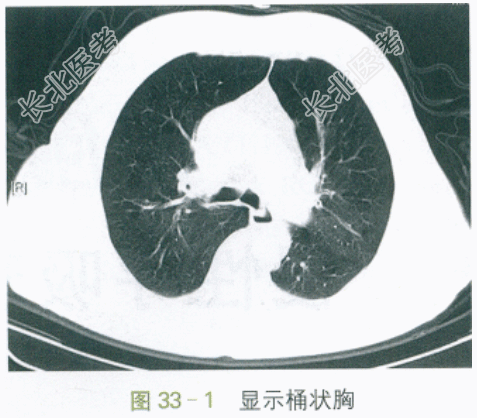

T37.2℃,P110次/min,R25次/min,BP145mmHg/88mmHg,神志清,神萎,呼吸急促,口唇发绀,球结膜水肿,颈软,颈静脉充盈,气管居中,桶状胸,双肺叩诊清音,听诊呼吸音粗,呼气相延长,两肺可及哮鸣音,未及湿啰音。HR110次/min,律齐,可及早搏。双下肢轻度凹陷性水肿。神经系统体征(-)。

胸部平扫CT:肺气肿,两肺少量慢性为主炎症。如图33-1、图33-2所示。